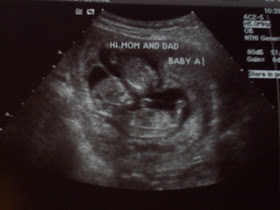

12 Week Dating / Nuchal Scan The 12 week dating / Nuchal scan can actually be done from 11 to 14 weeks and has a number of benefits, and so is essential in all pregnancies . The majority of miscarriages happen before this stage of pregnancy and so knowing all is well on scan by this stage gives parents a significant amount of reassurance .

12-week scan . If you're pregnant in England you'll be offered an ultrasound scan at around 10 to 14 weeks of pregnancy . This is called the dating scan . It's used to see how far along in your pregnancy you are and check your baby's development . The scan may also be part of a screening test for Down's syndrome .

What is the 12 week NT scan ? The 12 week scan is a routine ultrasound examination carried out at 10 to 14 weeks of gestation . During the examination, the fetus is seen by abdominal ultrasound . Occasionally the view is not clear and it may be necessary to perform a vaginal scan .

The nuchal translucency scan is best done during the 12th week , but it can be done from 11 weeks and 3 days up until 14 weeks and your local NHS hospital will offer you an appointment to have this done at around this time . Nevertheless, some parents may opt to have this done privately instead .

A nuchal translucency scan is part of the ultrasound scan that most pregnant women have at around 12 weeks of pregnancy . If you decide to have the scan , the health professional performing the ultrasound will measure your baby's nuchal translucency (a fluid-filled space at the back of your baby's neck) . The results of a nuchal translucency scan may . . .

What will I find out at the 12-week scan ? The dating scan is the first time you (or anyone) will have seen your baby so there's a few things that your sonographer will look out for and things you'll find out: β’ How many weeks pregnant you are, and your EDD (estimated date of delivery) .

The 12-week scan or dating scan Although sometimes known as the reassurance and viability scan , your 12 week scan is more typically referred to as the dating scan . Bear in mind that you may not have your scan at exactly 12 weeks ; it usually takes place between your 10th and 14th week of pregnancy 1 .